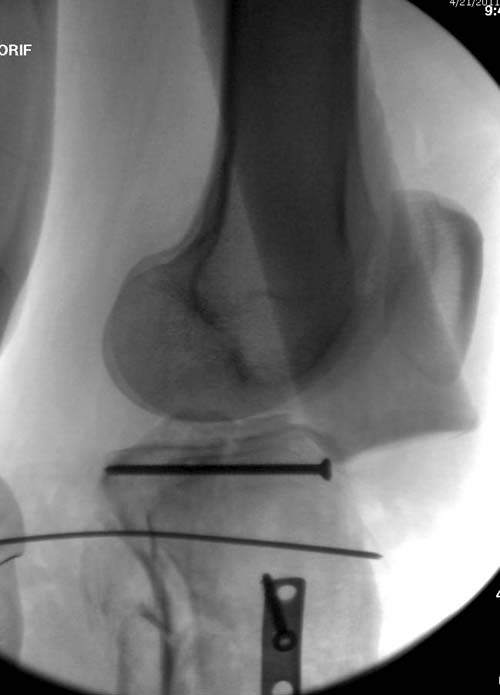

Вытяжение или наружный фиксатор “бедро-голень в виде дельты”. Фиксатор дает свободу, и если условия позволяют, можно отпускать домой. Но главное - надо ожидать проявления “wrinkle sign”! После дистракции можно делать КТ исследование, иначе нестабильные фрагменты искажают данные. Доступ делается по топографии расположения фрагментов, а 3Д картина лучше покажет расположение смещенных мыщелков.

На боковом рентгене, явный задний смещенный компонент. КТ поможет увидеть "вершину" перелома, куда надо поставить антискользящую пластину из заднего или задне-медиальнего доступа. Для стабилизации боковой колонны традиционный боковой доступ через Girdle tubercle с длинной блокирующей пластиной. Одна задняя подпорка не удержит медиальную колонну, требуется длинная медиальная пластина.

Еще надо быть готовым к импрессионному перелому, который надо поднять и заместить. Закрыть дефект можно любым пластическим материалом, а наличие алло-материалов облегчает процесс и предупреждает осложнения в области донорского участка.